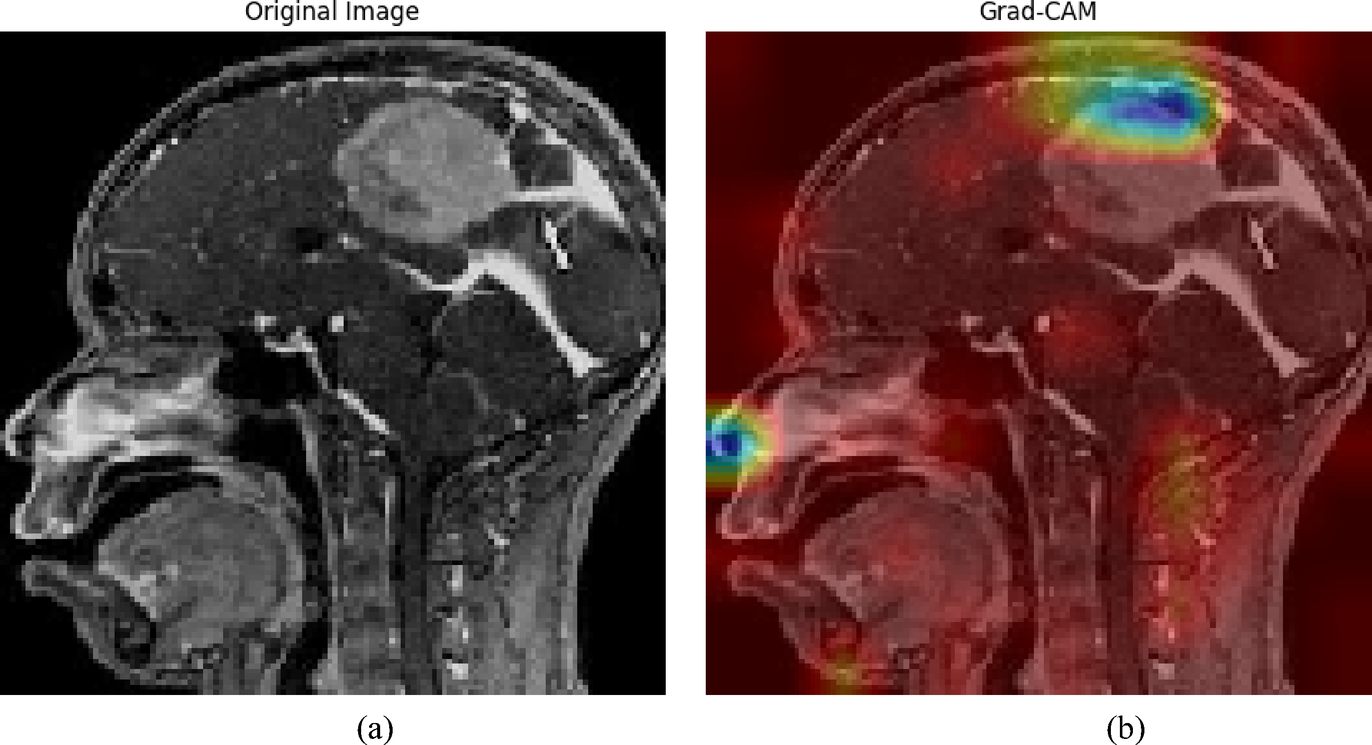

Original image (a) and Grad-CAM XAI heatmap (b).